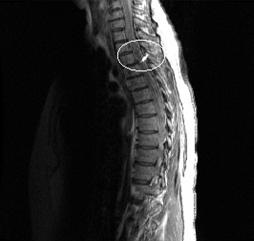

Star artifact

The Star artifact is a peripheral signal artifact that appears as a bright spot close to the middle of the image. This artifact is caused from signals generated outside the desired FOV that are detected by the receiver. Star artifact signals originate very far from isocenter. In that non-linear region, the FID signal coming off the RF 180 pulse or from a SAT pulse is not crushed out and aliases back into the image.

The FSE sagittal thoracic spine image below presents a Star artifact. The image was acquired with spine48, 28 cm FOV, and the phase and frequency swapped. The artifact could have been prevented by not swapping phase and frequency and using a 2-tile selection, such as spine32 so the surface coil coverage would closer match the scan FOV.